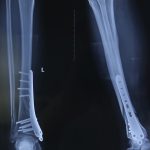

PHẪU THUẬT KẾT HỢP XƯƠNG BẰNG NẸP VÍT CHO NGƯỜI BỆNH “GÃY XƯƠNG CHÀY”

(benhvienhatrung.vn) – vừa qua các bác sĩ Khoa Ngoại Bệnh viện Đa khoa Hà Trung thực hiện thành công ca phẫu thuật kết hợp...